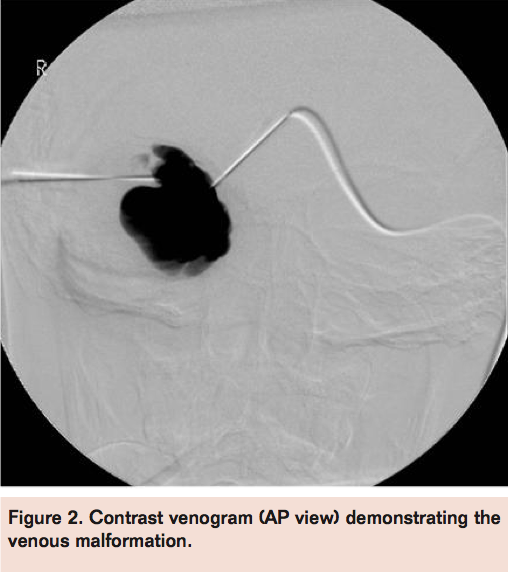

The procedure was performed in a digital subtraction angiography suite (Siemens Multistar T.O.P.), under general anesthesia with aseptic precautions. Dexamethasone 0.1 mg/kg was given intravenously. Ultrasound guidance was used for the initial access using two 23 g scalp vein needles (Figure 1).